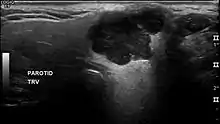

Pleomorphic adenoma in ultrasound

In terms of imaging studies, ultrasound can determine and characterize superficial parotid tumors. Certain types of salivary gland tumors have certain sonographic characteristics on ultrasound.[4] Ultrasound is also frequently used to guide FNA or core needle biopsy.